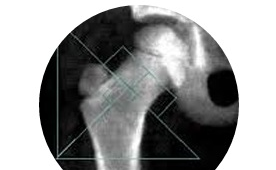

OSTEODENSITOMETRIE

L’ ostéodensitométrie est une technique d’imagerie qui utilise les rayons X pour acquérir des images qui sont spécifiquement utilisés pour mesurer la densité des os. Comme les rayons X passent à travers l’os, ils créent des densités différentes sur une plaque d’imagerie. Ces densités et donc la quantité de rayons X qui atteignent la plaque sont utilisés pour analyser la densité de l’os qu’ils ont passé à travers.